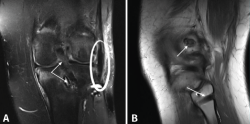

Todos los pacientes fueron intervenidos por el mismo cirujano. El tratamiento se adaptó a cada caso, realizando reconstrucción temprana (primeras 3 semanas) en un solo tiempo siempre que fue posible(7,12). Se realizó reconstrucción mediante aloinjertos: con tendón tibial anterior para las plastias de LCA, hemitendón de Aquiles con pastilla ósea para las plastias de LCP y LCM, y semitendinoso y/o recto interno para las reconstrucciones del CPL(17). En los casos de lesión del CPL con avulsión de la cabeza del peroné, se realizó reparación mediante reinserción ósea(18). Para el LCA se utilizó una técnica anatómica con fijación femoral con dispositivo de suspensión cortical (EndoButton®, Smith & Nephew, Londres, Reino Unido) y fijación tibial con tornillo interferencial reabsorbible (BioRCI®, Smith & Nephew, Londres, Reino Unido). Para el LCP se realizó reconstrucción anatómica artroscópica(19) con fijación femoral y tibial con tornillo interferencial (Figura 2), excepto en un caso en el cual se realizó ligamentoplastia con fijación femoral con tornillo interferencial y abordaje directo posterior en la tibia, con fijación tibial con pastilla ósea y tornillo de osteosíntesis según la técnica de inlay(20). El CPL se reconstruyó mediante ligamentoplastia según técnica de Arciero(21) con fijación femoral y en el peroné con tornillos interferenciales (Figuras 2 y 3). El CPM se reconstruyó en función de las estructuras dañadas, con ligamentoplastias anatómicas con fijación con tornillos interferenciales(22).

Figura 2. Paciente con lesión KD I (lesión del ligamento cruzado posterior –LCP– y el complejo posterolateral –CPL–). A: corte coronal de resonancia magnética (RM) postoperatoria en el que se muestra la plastia del LCP y el tornillo interferencial de fijación tibial de la misma (doble flecha blanca), así como la plastia del ligamento femorofibular (círculo blanco); B: corte sagital de RM postoperatoria en el que se muestra uno de los túneles femorales para la plastia del CPL (flecha superior), así como el túnel en el peroné para dicha plastia (flecha inferior).